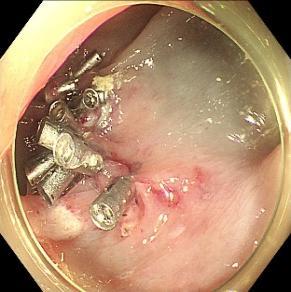

• 可旋转重复开闭软组织夹联合外科尼龙缝合线法闭合结直肠内镜黏膜下剥离术后缺损的临床应用价值

2025, 31(12):77-82. DOI: 10.12235/E20250091

摘要 (77) HTML (65) PDF 1.86 M (64) 评论 (0) 收藏

摘要:目的 探讨可旋转重复开闭软组织夹联合外科尼龙缝合线法(ROLM)闭合结直肠内镜黏膜下剥离术(ESD)后黏膜缺损的临床疗效。方法 回顾性分析2024年1月-2024年6月15例在南京医科大学附属常州市第二人民医院因早期结直肠肿瘤行ESD,并采用ROLM闭合黏膜缺损患者的临床资料。观察患者病灶相关情况(病灶部位、缺损最大径和术后病理)、手术相关情况(术后缺损成功闭合率、钛夹使用数量、ROLM缝合时间和住院时间)、术后并发症发生情况和术后随访情况。结果 术后缺损成功闭合率为100%。病灶长径3.0~6.0 cm,平均(3.7±0.8)cm。缺损部位:回盲部1例,升结肠6例,横结肠肝曲1例,降结肠2例,乙状结肠3例,直肠2例。术后病理为:管状腺瘤8例,黏膜下囊肿1例,管状绒毛状腺瘤5例,胃肠道间质瘤1例。钛夹使用数量为7~20枚,中位数为11(10,13)枚。ROLM缝合时间为13~37 min,平均(19.3±6.5)min。住院时间4~9 d,平均(6.5±1.2)d。术后无出血、穿孔、感染和消化道狭窄等并发症发生。术后3~6个月复查肠镜,手术创面均愈合良好。结论 ROLM能够安全、有效地闭合结直肠ESD后黏膜缺损。值得临床推广应用。